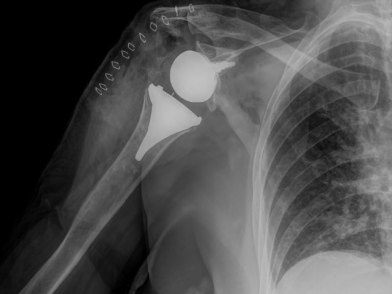

Υπάρχουν ουσιαστικά τρεις παραλλαγές της αρθροπλαστικής ώμου: η ημιαρθροπλαστική (shoulder hemiarthroplasty – ΗΑ), όπου μόνο η αρθρική επιφάνεια του βραχιονίου κεφαλής αντικαθίσταται με μία προσθετική, η ανατομική ολική αρθροπλαστική ώμου (Total Shoulder Arthroplasty – TSA), όπου τόσο η ωμογλήνη όσο και η βραχιόνιος κεφαλή αντικαθίστανται από προθέσεις όμοιας καμπυλότητας με τις αρχικές επιφάνειες, και τέλος, η ανάστροφη ολική αρθροπλαστική ώμου (Reverse Shoulder Arthropasty – RSA), όπου αμφότερες οι αρθρικές επιφάνειες αντικαθίστανται από προθέσεις αντίθετης καμπυλότητας με τις αρχικές.

Η επιλογή μεταξύ των προαναφερθεισών τύπων προθέσεων εξαρτάται κυρίως από τη βιολογική ηλικία του ασθενούς, την κατάσταση των μυών του στροφικού πετάλου και την ακεραιότητα των τενόντων τους, καθώς και την ακριβή ένδειξη για την αρθροπλαστική ώμου. Η ανατομική ολική αρθροπλαστική ώμου ενδείκνυται γενικότερα για την πρωτοπαθή και τη δευτεροπαθή οστεοαρθρίτιδα του ώμου, υπό την προϋπόθεση ότι υπάρχει επαρκές οστικό υπόβαθρο στην ωμογλήνη, ότι οι μυς του στροφικού πετάλου και ο δελτοειδής είναι ακέραιοι και λειτουργικοί, ότι το βραχιόνιο πλέγμα (το μείζον νευρικό πλέγμα που νευρώνει το άνω άκρο) είναι πλήρως λειτουργικό, ότι δεν υπάρχει προς τα άνω μετατόπιση της βραχιονίου κεφαλής γεγονός που θα υποδείκνυε την παρουσία αρθροπάθειας του στροφικού πετάλου, καθώς και ότι δεν υπάρχει κάποια ένδειξη ενεργού λοίμωξης. Η ημιαρθροπλαστική του ώμου από την άλλη πλευρά, ενδείκνυται είτε σε περιπτώσεις πρωτοπαθούς αρθρίτιδας όπου το στροφικό πέταλο είναι ανεπαρκές ή το οστικό υπόβαθρο της ωμογλήνης υπολείπεται, είτε σε νεότερους ασθενείς και χειρώνακτες εν ενέργεια, λόγω της αυξημένης πιθανότητας χαλάρωσης της πρόθεσης της ωμογλήνης σε αυτές τις ηλικιακές ομάδες. Ενδείκνυται επίσης σε επιλεγμένες περιπτώσεις αρθροπάθειας του στροφικού πετάλου, στην οστεονέκρωση της βραχιονίου κεφαλής χωρίς συμμετοχή της ωμογλήνης, σε ορισμένα 3 τεμαχίων και στα περισσότερα 4 τεμαχίων κατάγματα εγγύς βραχιονίου, και σχεδόν σε όλα τα ενδαρθρικά κατάγματα της βραχιονίου κεφαλής σε ασθενείς νεότερους από 65 έως 70 ετών. Τέλος, η ανάστροφη πρόθεση ενδείκνυται σε πιο ηλικιωμένους ασθενείς με αρθροπάθεια του στροφικού πετάλου, στην οστεοαρθρίτιδα του ώμου με συνοδό, μη επιδιορθώσιμη ρήξη του στροφικού πετάλου, στα τριών και τεσσάρων τεμαχίων κατάγματα εγγύς βραχιονίου καθώς και στα ενδαρθρικά κατάγματα της βραχιονίου κεφαλής σε ασθενείς μεγαλύτερους από 70 ετών ή με σοβαρή οστεοπενία, στη ρευματοειδή αρθρίτιδα του ώμου, υπό την προϋπόθεση ότι υπάρχει επαρκές οστικό υπόβαθρο στην ωμογλήνη και, τέλος, μετά από αποτυχημένη ημιαρθροπλαστική ή ανατομική αρθροπλαστική ώμου. Σημειωτέον ότι για να είναι επιτυχημένη η ανάστροφη αρθροπλαστική ώμου είναι επιτακτικής σημασίας να είναι ακέραιος και λειτουργικός ο δελτοειδής μυς.